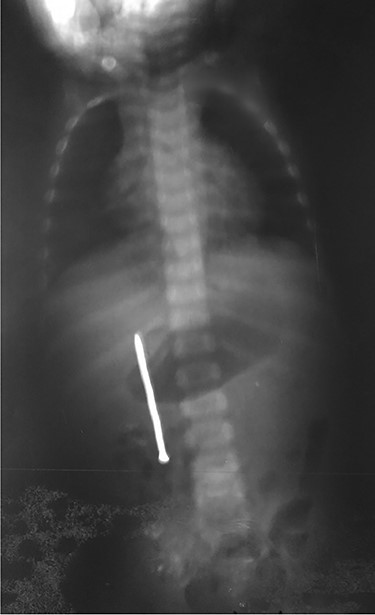

A 3-year-old male child was admitted in surgery department, with history of accidental ingestion of construction nail for 30 days, without any symptoms. Parents consulted in a peripheral hospital and plain abdominal radiography showed a nail projected in right-edge upon the lumbar spine (Fig. 1). Clinical observation was advised. The nail did not pass spontaneously and the child remained asymptomatic. Parents decided to consult again, but in our institution (surgery department). The child did not experience fever nor digestive symptoms (nausea, vomiting, abdominal pain, blood or color changes in stool). He had no prior history of FB ingestion.

Plain radiography plays the main role both in the diagnosis and the choice of operative interventional moment—either by pinpointing the radio-opaque image, or by showing certain FB characteristics, or by noting images suggesting complications (absent in our case), or even by projecting the FB in the same place over a period of time, an aspect inductive of fistula. In our case, right-edge superposition of the FB image upon the lumbar spine is characteristic of FB positioning in the second part of duodenum [5, 6]. Its persistence in the same place (the second part of the duodenum as in our case) suggests the presence of a duodenal fistula or perforation, which requires surgical intervention [7].